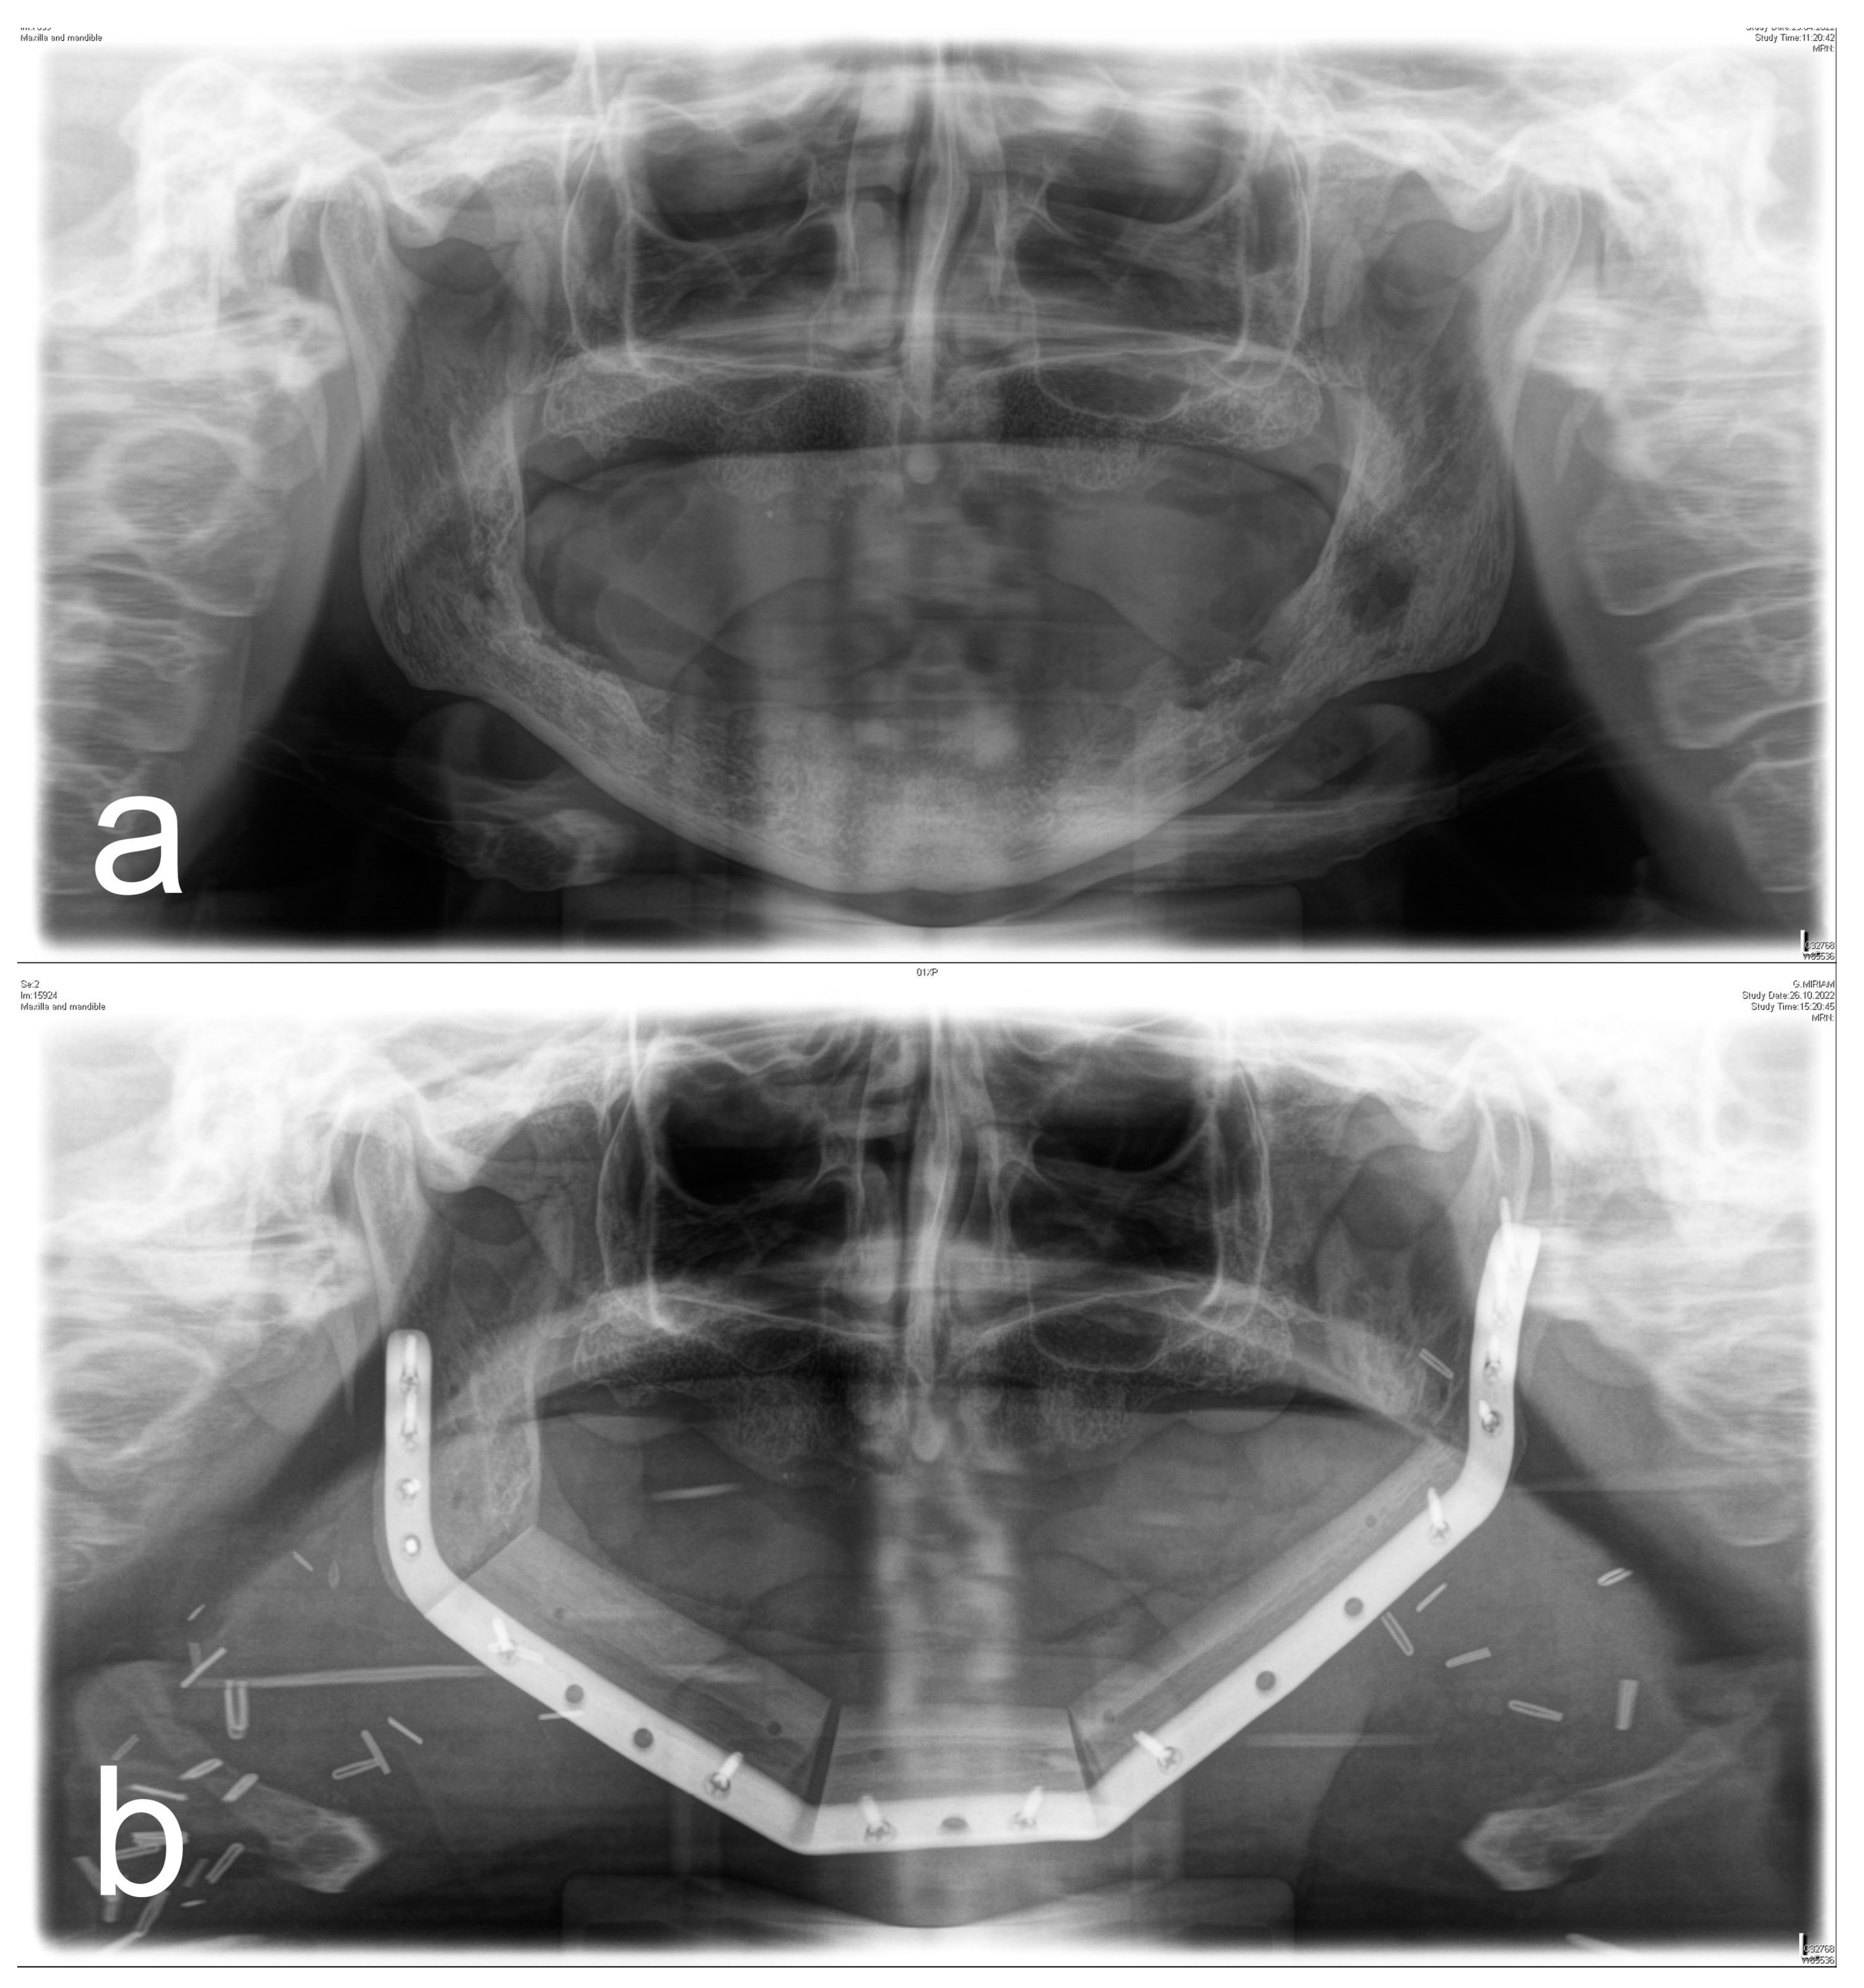

Figure 1, Figure 2, Figure 3 and Figure 4 illustrate two cases of advanced mandibular resection with severe hard and soft tissue injury followed by reconstruction using a vascularized fibula flap. This graft allows reconstruction of bone and soft tissue, the latter of which can be used to replace extraoral skin (Figure 2) or intraoral mucosa (Figure 4).

Figure 3. (a) Panoramic X-ray of a patient with extensive ORN of the mandible. (b) Postoperative panoramic X-ray of the same patient after ablative and reconstructive surgical therapy of ORN using a vascularized 3-segment fibula flap with an extraoral soft tissue transfer and a patient-specific implant.